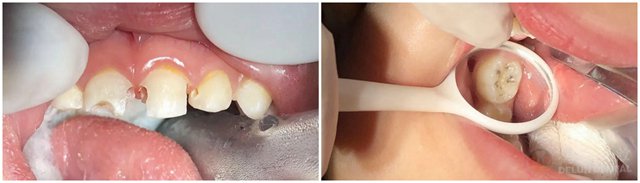

很多小宝贝对看牙有巨大的心理阴影,由于疼痛、不舒服、器械运转声音等缘故,往往会逃避检查,不配合医师的诊疗。通过非常可靠、舒适的儿童舒眠麻醉诊疗技术,小朋友只要睡一觉,就能可靠舒适的完成治疗,给孩子一个没有压力、没有恐惧的治疗环境,保持口腔健康,从此不再害怕看牙。

“对于一些非常抗拒治疗的孩子而言,如果不进行儿童舒眠麻醉,反而会增加手术风险,这绝不是危言耸听。”张景棋医生表示,“没有儿童舒眠麻醉,孩子在手术时可能不会全程配合,后果就是他不停地动,对手术的精细程度产生巨大影响,即使进行束缚治疗,一旦手术过程孩子出现剧烈反抗,后果不堪设想。”

那么,哪些小朋友适合做儿童舒眠麻醉诊疗呢?张景棋医生介绍到,1. 极度恐惧儿童,患儿无法配合常规口腔治疗者;2. 患儿有多颗牙需要治疗,且无多次就诊条件(如外地,家离医院太远);3. 患儿有智力或全身疾病等方面的问题(比如自闭症、脑瘫,智力障碍等);4. 监护人担心捆绑束缚下牙齿治疗可能会对患儿心理造成伤害,使用全身麻醉可以保护其心理免受伤害并避免医疗危险。